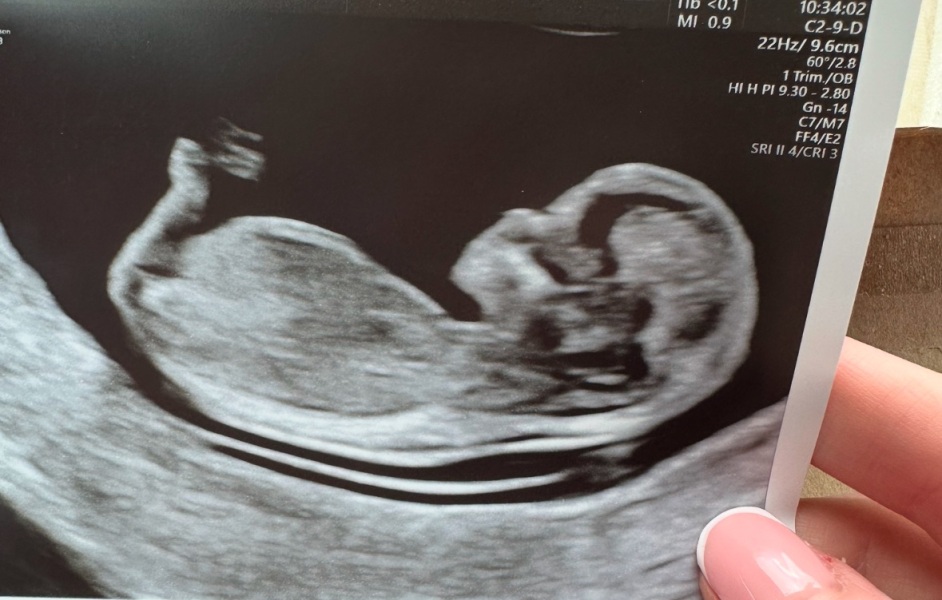

Would anyone care to guess the gender of our first baby. This is our 12 week scan.

A little girl 😊

Looks so much like my little girls scan plus perfect little head where as my son his head was noticeably more blocky. I feel I'm not seeing the nub due to being girl.. keep me updated please 😊

Yep pretty sure that’s a girl.